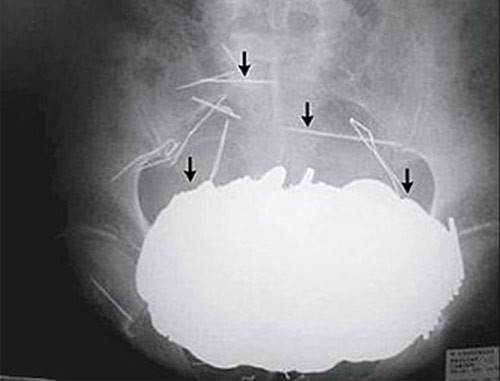

Cô Nicole Haynes đã qua đời bất ngờ sau 1 ca phẫu thuật nội soi ổ bụng đơn giản. Sau đó nhân viên bệnh viện đã phát hiện một đoạn phim ghi lại toàn bộ quá trình phẫu thuật. Nội dung đoạn phim cho thấy, các bác sĩ chịu trách nhiệm về ca mổ đã bỏ quên… kéo trong bụng bệnh nhân và không thực hiện đầy đủ những thao tác cần thiết khi hoàn thành phẫu thuật.